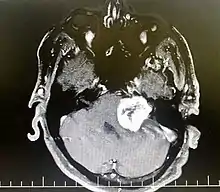

| Bilateral schwannomas in a patient with neurofibromatosis 2 | |

از علائم این بیماری وزوز مداوم گوش و به تدریج کاهش شنوایی و عدم تعادل است. تومورهای زاویه مخچه – پل مغزی فشار به اعصاب جمجمهای مخچه –ساقه مغز و بطن چهارم ایجاد میکنند . فراوانترین علامت در نوروم آکوستیک کاهش شنوایی (در ۸۷٪ بیماران) و وزوز گوش است. شمار کمتری از این بیماران سردرد، سرگیجه و بی حسی صورت دارند. نورم آکوستیک در دهههای ۳تا ۵ شایعتر است. آکوستیک نوروما (AN) در 95 % موارد یک طرفه و حدود 5 % دو طرفه است. نوع دوطرفه آن بسیار نادر رخ می دهد که مرتبط با یک سندرم ارثی به نام نوروفیبرو ماتوزیس نوع دوم (NF2) می باشد. تومور آکوستیک تومور مغزی نیست. این تومور در واقع یک تومور عصب تعادل است و نام علمی تر آن شوانوم وستیبلار می باشد.